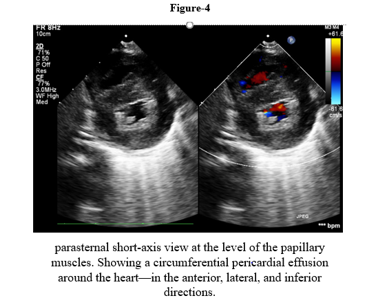

We report a four-month-old girl who presented in sudden cardiorespiratory collapse to illustrate an uncommon cardiac first sign of MTO1-related disease. The infant arrived hypotensive and obtunded with severe metabolic acidosis (pH 6.59; lactate 29 mmol/L). Chest radiograph showed cardiomegaly and bedside echocardiography revealed a large circumferential pericardial effusion producing compression of the right heart together with concentric left-ventricular hypertrophy. Emergency pericardiocentesis drained 120 mL of serous fluid and produced only transient improvement; over a prolonged PICU stay she had recurrent sterile effusions, four failed extubation attempts, refractory lactic acidosis, renal dysfunction and progressive bradycardia. Whole-exome sequencing identified a homozygous pathogenic MTO1 variant (NM_012123.4:c.1232C>T; p. Thr411Ile); both parents were heterozygous carriers. The family history included consanguinity and a sibling who died in early infancy after a similar illness. Despite maximal supportive care, she died on day 40 from cardiogenic shock and multiorgan failure. The case highlights that recurrent sterile pericardial effusion in an infant with hypertrophy and marked hyperlactatemia should prompt consideration of an underlying mitochondrial (MTO1-related) disorder and early genetic testing to guide counselling

This case illustrates tamponade as the initial cardiac manifestation of COXPD10. In infants, large effusions leading to tamponade should typically give rise to strong concerns for an infected, malignant, autoimmune, or post-surgical cause. Sterile recurrent effusions in addition to hypertrophic cardiomyopathy, in our patient, were suggestive of a metabolic cardiomyopathy.

Cardiomyopathy is a hallmark of COXPD10: O’Byrne et al. reported lactic acidosis in all 35 patients and cardiomyopathy in ~79% [2]. Zhou et al. described an infant with acidosis and early death [3], and Luo et al. reported another with compound heterozygous MTO1 variants and HCM [4]. Our case aligns with this phenotype but our case is distinctive in that it highlights pericardial tamponade as the critical event. The recurring effusions support a role of mitochondrial energetic failure in the development of capillary leak and edema. Within combined oxidative phosphorylation deficiencies, COXPD10 and COXPD23 (GTPBP3 mutations) in the audio-metabolic spectrum, both manifest with life-threatening HCM and acidosis age of onset of 1 year [8]. In contrast, COXPD1 (GFM1) and COXPD4 (TUFM) frequently present with hepatic failure and encephalopathy [9,10]; COXPD7 (C12orf65) has a later onset and symptomatology of neuro-ophthalmologic disease and uncommon cardiac disease [8]. So, in the setting of HCM and a sterile effusion, mitochondrial translation defects, in particular MTO1 and GTPBP3, should be considered by the cardiologist. Pericardiocentesis is life-saving for tamponade, but does not address the etiology, and recurrences occur in over 50%. The so-called mitochondrial contraceptive "cocktail" is widely utilized, though without evidence of aneuropathy efficacy in COXPD10 [2,4]. Dichloroacetate may also decrease lactate temporarily, but does not affect outcome [2,12]. Current approaches therefore do not alter disease course, and aggressive supportive care and counseling are issues of central management.